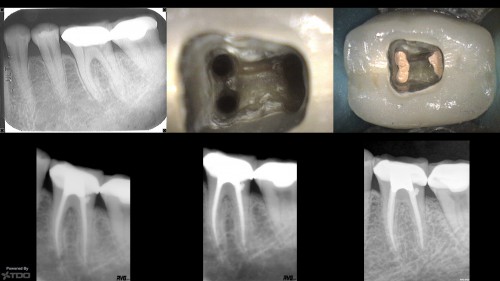

3 yr ECIR repair recall

By Gary Carr / July 20, 2018

I struggled with the composite. I think I could do it better today but at […]